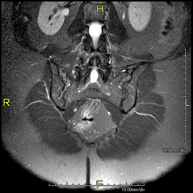

- RM Columna lumbar

Prueba diagnóstica no invasiva que consiste en la obtención de imágenes de alta definición anatómica de la lumbar y sacra, mediante el empleo de un campo electromagnético y ondas de radio (con un emisor y un receptor). No utiliza radiación ionizante. Indicaciones: traumatismos, ciática, hernias discales, tumores, infecciones.

Prueba diagnóstica no invasiva que consiste en la obtención de imágenes de alta definición anatómica de la lumbar y sacra mediante el empleo de un campo electromagnético y ondas de radio (con un emisor y un receptor). No utiliza radiación ionizante. Indicaciones: traumatismos, ciática, hernias discales, tumores, infecciones.